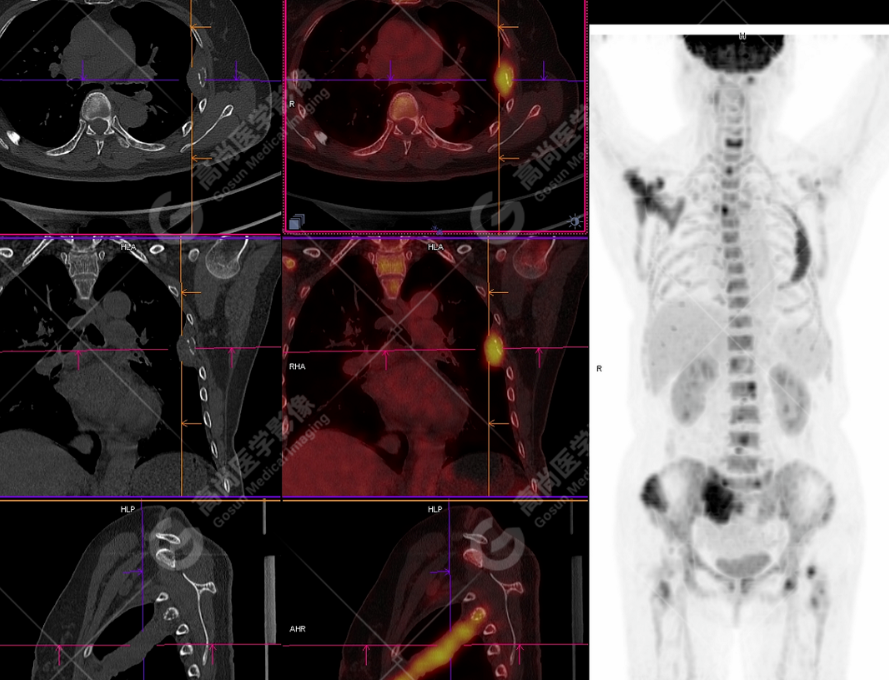

颅骨、寰椎前弓左侧份、第 6 颈椎、双侧肩胛骨(右侧为著)、左侧第 4 肋骨、第 1 胸椎、第 4 胸椎、第 2 腰椎及附件、第 4 腰椎及附件、骶骨、右侧髂骨、左侧坐骨结节、左侧股骨颈、双侧股骨小转子等均不同程度骨质吸收、破坏,其中右侧肩胛骨、左侧第 4 肋骨及骶骨右侧份软组织肿块影形成,上述病变均考虑恶性肿瘤(血液系统来源,多发骨髓瘤可能性大),建议右侧髂骨翼穿刺活检明确。

(4)PET-CT 影像表现:在溶骨性破坏区出现相重叠的 18F- FDG 高代谢区;通常呈弥漫性高代谢区。